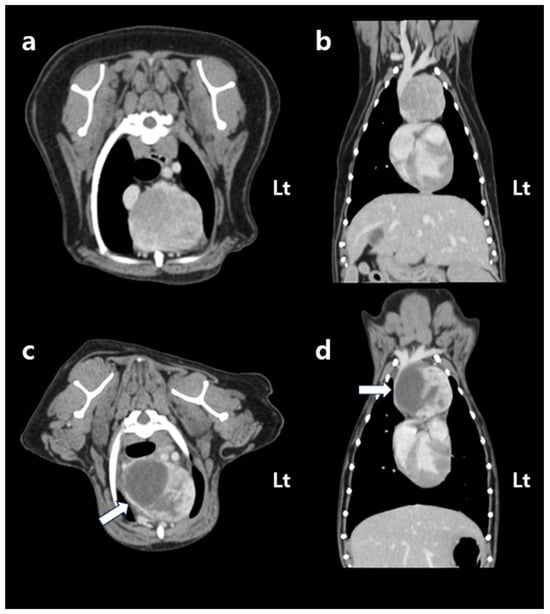

The dog remained clinically stable throughout the SBRT course. The dog completed all three planned SBRT fractions without treatment interruption and remained clinically stable under anesthesia during all sessions. However, the day after the final fraction (5 days after the first fraction), the dog developed acute dyspnea, characterized by increased inspiratory effort and mild open-mouth breathing. Clinical signs of anemia were also evident, as the mucous membranes appeared markedly pale, capillary refill time was prolonged to approximately 2.5 s, and the patient exhibited lethargy with reduced responsiveness to external stimuli. Hematologic testing revealed decreased platelet count (124 × 103/μL), red blood cell count (4.04 × 106/μL), hemoglobin (9.0 g/dL), and hematocrit (28.8%). To rule out an underlying coagulopathy, coagulation testing was performed, and the results showed that PT (10.4 s; reference range: 5–15 s), aPTT (29.2 s; reference range: 15–45 s), and fibrinogen concentration (2.7 g/L; reference range: 1–3 g/L) all remained within normal limits. Thoracic radiographs showed increased cranial mediastinal width (74.5 mm), swelling in submandibular and axillary regions, and pleural effusion (Figure 4). On palpation, the swelling in the bilateral submandibular and axillary regions was cool to the touch, soft, and pitting, with well-defined margins. There was no local warmth, erythema, or pain on palpation. The swelling was symmetrical and corresponded anatomically to the drainage area of the cranial vena cava, suggesting congestion secondary to venous compression rather than inflammatory or neoplastic infiltration. Thoracic ultrasonography revealed a heterogeneous, hypoechoic mass adjacent to the mediastinal lesion, with no detectable vascular flow signals on color Doppler imaging. Transthoracic echocardiography demonstrated a decreased left ventricular internal dimension during both diastole and systole, with preserved global systolic and diastolic function, and no evidence of structural cardiac abnormalities. Anechoic fluid accumulation was observed between the lung parenchyma and thoracic wall, consistent with pleural effusion (Figure 5). Based on the imaging and hematological findings, cranial vena cava compression secondary to tumor-related hemorrhage and hematoma formation associated with the irradiated mass was considered the most likely diagnosis. Other possible differential diagnoses included a necrotic portion of the tumor, abscess formation with inflammation, or a metastatic lesion.

At follow-up, the dog remained in a stable condition, with normal respiratory function and no recurrence of swelling in the submandibular or axillary region. Follow-up CT was performed on day 33 post-SBRT (37 days after the first fraction of SBRT), not primarily to assess tumor shrinkage but rather to evaluate potential treatment-related complications. Specifically, the scan was intended to monitor for tumor-associated hemorrhage and hematoma formation, to assess compression of adjacent vascular and mediastinal structures, and to rule out bleeding from surrounding normal organs. The CT showed an overall increase in tumor dimensions (length: 42.1 mm; width: 49.0 mm; height: 40.0 mm). Tumor volume increased from 25.0 cm3 to 46.4 cm3; however, the contrast-enhancing portion decreased by approximately 25% to 18.7 cm3. This decrease was accompanied by a relative increase in the non-enhancing component of the mass (pre-contrast: 30 HU; post-contrast: 31.5 HU), which exerted compression on the cranial vena cava (Figure 1c,d). Based on imaging features, hematologic findings, and the clinical course, the non-enhancing region was interpreted as a tumor-related hemorrhage secondary to radiation therapy. Thoracic radiography performed on day 88 post-SBRT (92 days after the first fraction of SBRT) revealed a further reduction in the mediastinal width to 43.4 mm, with no evidence of pleural effusion (Figure 4). The dog remained clinically stable, without any evidence of dyspnea, lethargy, or other signs of anemia. At the last follow-up on day 143 after the first SBRT fraction (139 days after completion of the final fraction), the patient was still clinically stable without recurrence of dyspnea or anemia-related signs. Thoracic radiographs at that time showed no significant changes compared with those obtained on day 88 post-SBRT (Figure 4c).

Figure 1. Post-contrast CT images acquired before (a,b) and 37 days after (c,d) the first fraction of stereotactic body radiotherapy. Transverse images are shown in (a,c), and dorsal reconstructions are shown in (b,d). All images were obtained using a soft tissue algorithm (window level, 45; window width, 450). Before stereotactic body radiotherapy, the cranial mediastinal mass displays heterogeneous contrast enhancement and is located in close proximity to the cranial vena cava, right atrium, and right ventricle. CT performed 37 days after the first radiation fraction shows that the overall size of the mass has increased; however, the volume of the contrast-enhancing region has decreased by approximately 25%. The cranial vena cava is compressed by a newly developed non-enhancing region (white arrow). CT, computed tomography. Lt: left.